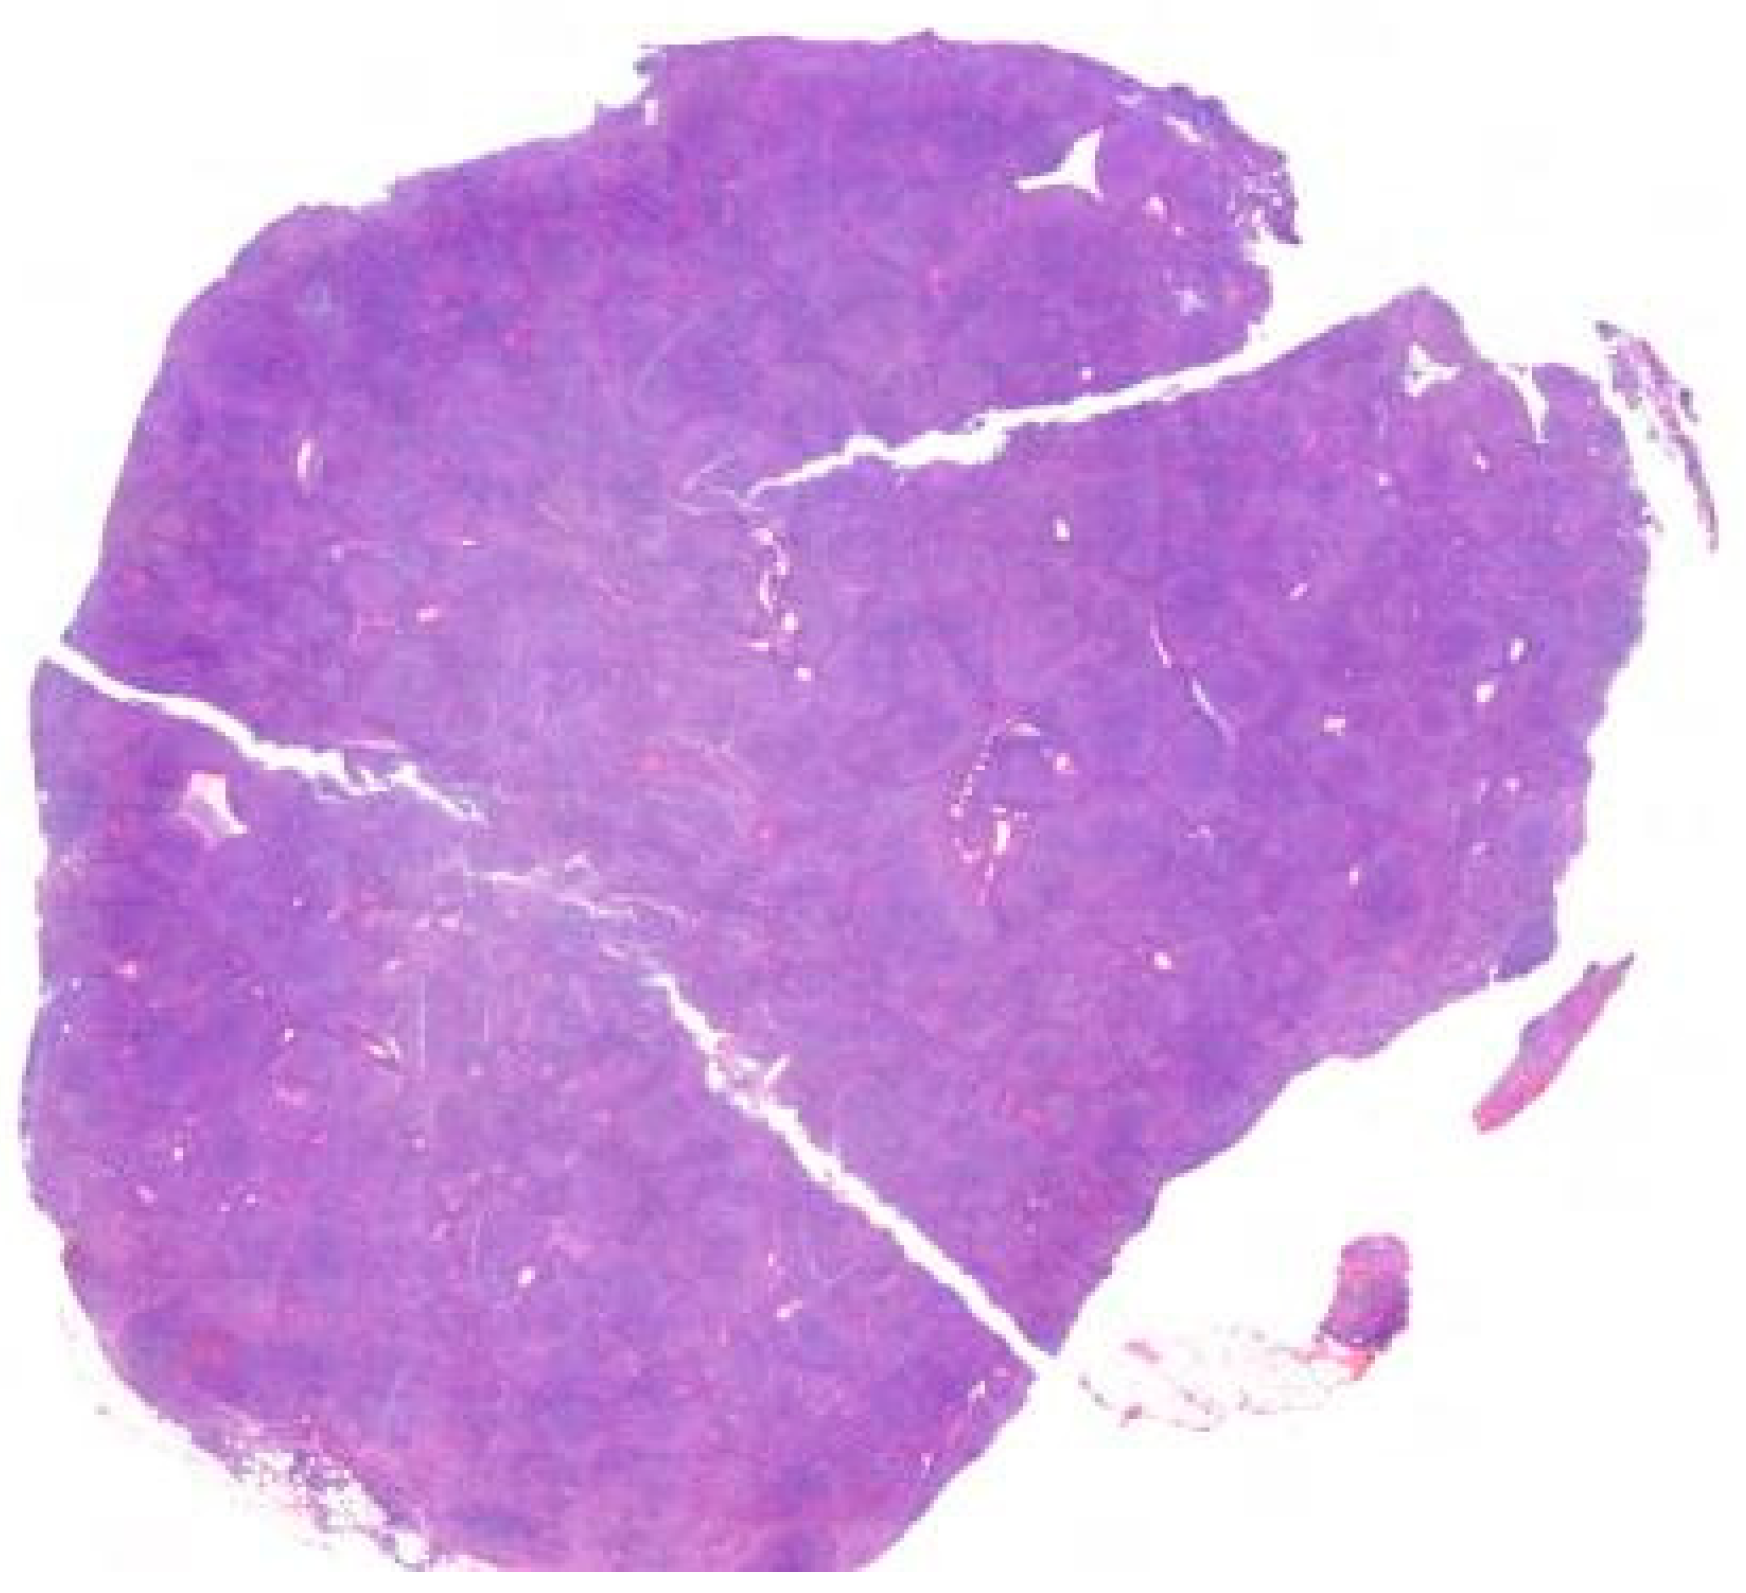

3.1. Chronic Lymphocytic Leukemia/Small B-Cell Lymphoma (Figure 5) [4,5,14,15]